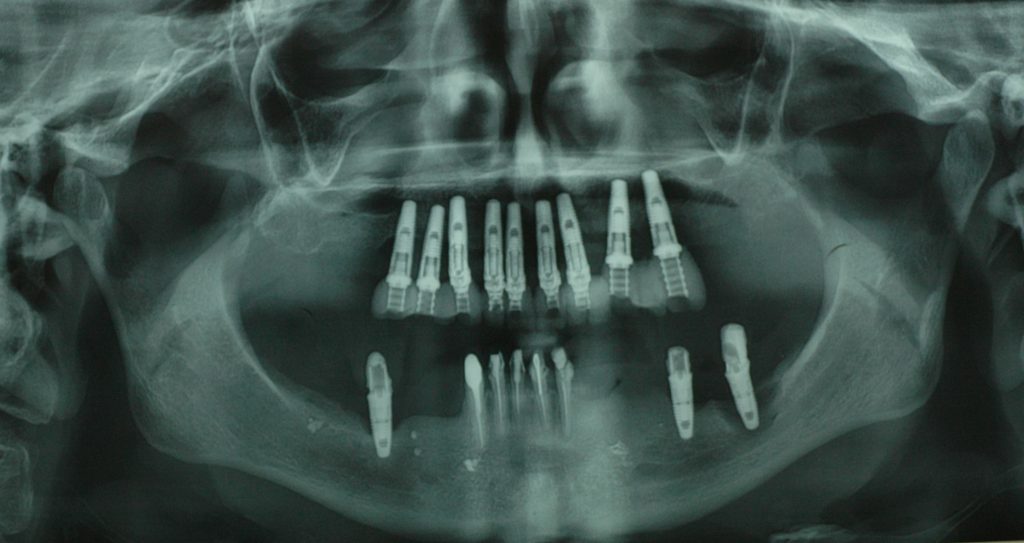

Streszczenie: W ostatnich latach w Polsce leczenie implantoprotetyczne staje się coraz bardziej powszechne. W związku z rosnącą częstością wykonywania zabiegów implantologicznych, które w części przypadków przeprowadzane są na granicy wskazań, wzrasta odsetek powikłań z tym związanych. Komplikacje powstające w trakcie terapii z użyciem implantów stomatologicznych mogą pojawić się na każdym z etapów leczenia, także w czasie, kiedy implant jest już obciążony pracą protetyczną. Problem powikłań będzie stawał się coraz częstszy, a kwestia ich leczenia będzie w przyszłości stanowiła znaczną część zagadnień związanych z implantologią.

Summary: In recent years in Poland implantoprosthetic treatment has become increasingly popular. Due to the increasing frequency of implantation procedures, which in some cases are carried out at the limit of indications, the proportion of complications increases. Complications arising during dental implant therapy may occur at any stage of the treatment, including the time when the prosthetic restoration is already placed on the implant. The problem of complications will become more and more frequent, and the issue of their treatment will be a significant part of the problems associated with implantology in the future.